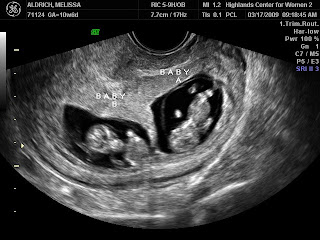

2009I had my second OB appointment last week and was just amazed to see how much the little ones had grown over the last month! They went from looking like little aliens:

to looking like sweet babies!